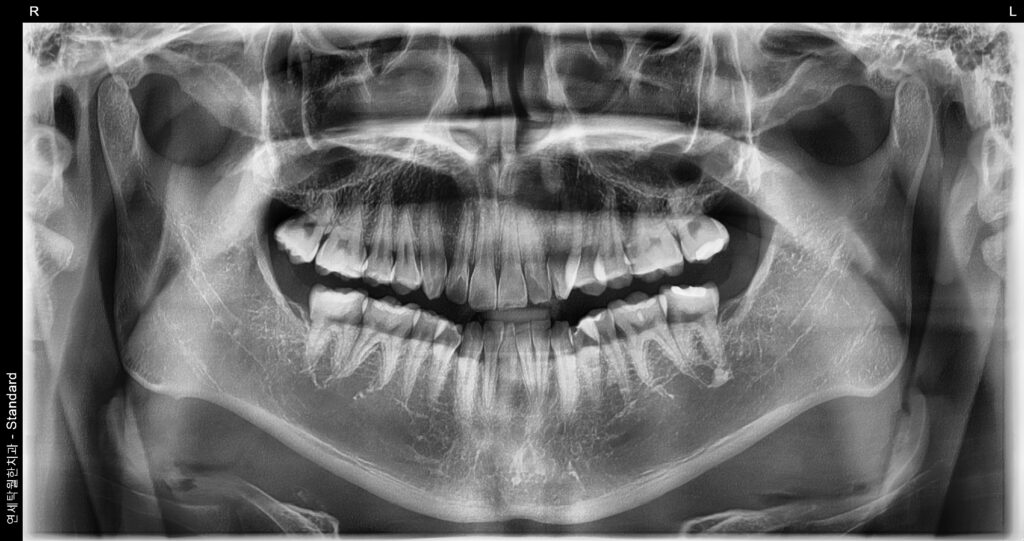

매복된 왼쪽 위 사랑니(#28) 발치 전 사진

위과 같이 상악 매복 사랑니가 어금니의 머리 밑으로 들어가 있는 경우 생각보다 사랑니 발치가 어려워지는 경우도 있습니다. 이럴 경우 매복 사랑니의 앞머리를 절단하여 빼야하기에 아주 난이도가 높은 수술로 바뀔 가능성이 있습니다. 이로 인해 사랑니 발치 시간이 길어지는 경우도 종종 발생하기에 간단히 생각하지 마시고 사진을 찍은 후 치과의사와 충분한 상담이 필요로 합니다.